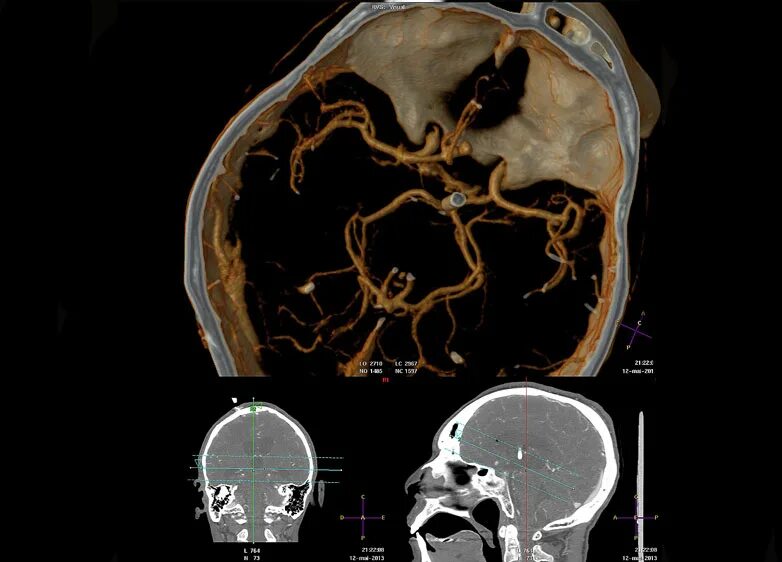

Аневризма головного мозга на кт